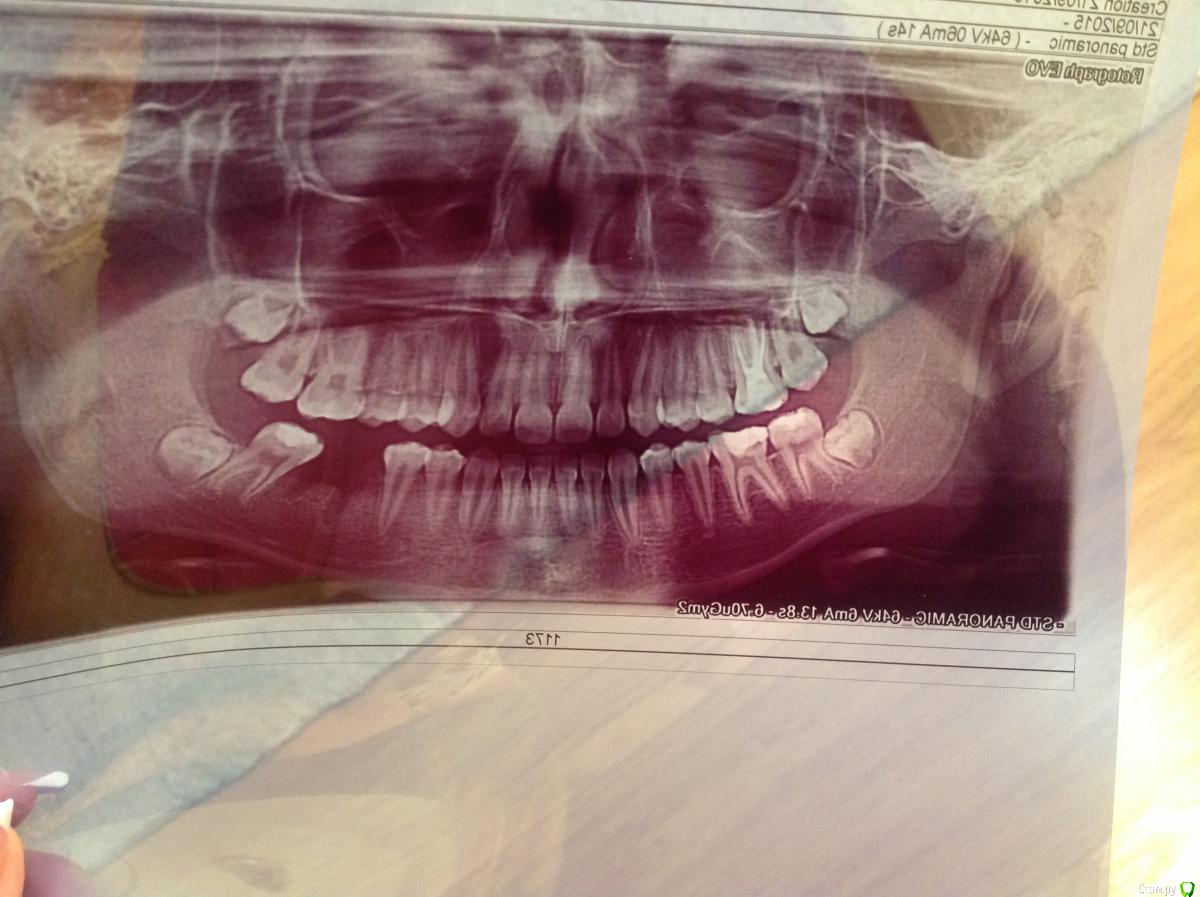

Elenavat Опубликовано 23 сентября, 2015 Поделиться Опубликовано 23 сентября, 2015 (изменено) Здравствуйте! Посоветуйте,пожалуйста, что делать! Мальчику 14 лет, две недели назад удалили 6 зуб на нижней челюсти. Изначально планировали сохранить место с помощью бабочки или колец для последующей имплантации. Направили на консультацию к ортодонту. Ортодонт сказала сделать снимок, и если есть зачатки 8 ки, то на место удаленного 6 зуба можно будет перетянуть 7, а 8 потом вылезет на месте 7. Подскажите пожалуйста, целесообразно ли такое перетягивание, или лучше сохранить место с помощью колец, а затем после 18 лет поставить имплантат? Снимок прилагаю. Заранее спасибо! Изменено 23 сентября, 2015 пользователем Elenavat Ссылка на комментарий